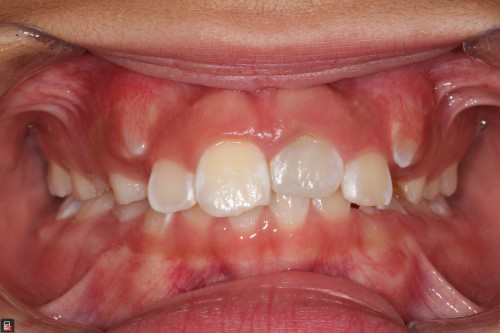

9yo girl, #9 ankylosis and discoloration

By Brandon Seto / August 2, 2018

Dear colleagues, I posted this to the AAE forum, and I’m hoping for input from […]

9yo girl, ankylosis and discoloration #9

Dear colleagues, I just posted this to the AAE forum, and I’m hoping TDO’ers could […]